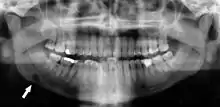

| Panoramic radiograph | |

![]() A dental panoramic radiograph, showing the maxilla and mandible, all the teeth including the "wisdom teeth," the frontal and maxillary sinuses, the nasal cavity and the temporomandibular joint and other near by head and neck anatomy. | |

A panoramic radiograph is a panoramic scanning dental X-ray of the upper and lower jaw. It shows a two-dimensional view of a half-circle from ear to ear. Panoramic radiography is a form of focal plane tomography; thus, images of multiple planes are taken to make up the composite panoramic image, where the maxilla and mandible are in the focal trough and the structures that are superficial and deep to the trough are blurred.